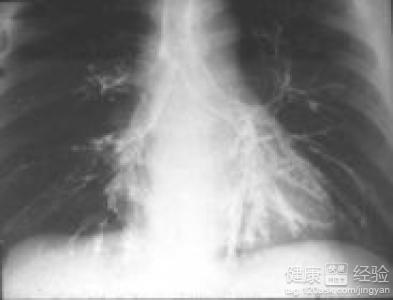

肺心病是由於肺部疾病導致肺動脈血壓升高,從而導致右心功能改變的一種疾病。主要表現為呼吸困難加重,頭昏等症狀,如不及時治療,病情會進一步加重。在感覺呼吸困難,心髒不舒服時應及時就診,以免耽誤最佳治療時機。